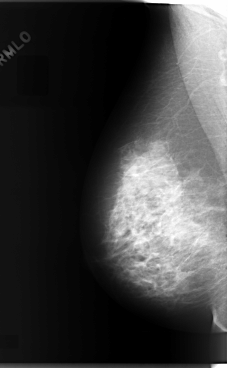

C_0070_1.RIGHT_MLO

RIGHT_MLO LINES 5888 PIXELS_PER_LINE 3640 BITS_PER_PIXEL 12 RESOLUTION 50 NON_OVERLAY